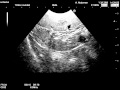

症例紹介:蛋白漏出性腸症~消化管型リンパ腫と腸リン. この症例では、腸壁の層構造が消失した腸管をみとめました。低エコー領域(黒い部分)が腸管の肥厚部位です。. 悪性リンパ腫とは|検査や治療、ステージなど【がん治. 白血病・悪性リンパ腫について、特徴・分類・検査方法・生存率など様々な観点から解説します。. 甲状腺がんとは|検査や治療、ステージなど【がん治療】. 超音波(エコー)検査 超音波を体の表面に当て、臓器から返ってくる反射の様子を画像にする検査。甲状腺の大きさや. 悪性リンパ腫<お年寄りの病気>とは|症状や原因・診. 悪性リンパ腫<お年寄りの病気>。Malignant lymphoma. 悪性リンパ腫の検査と診断 リンパ節や腫瘤(しゅりゅう)の一部を試験的. 神経芽腫 検査・診断:[国立がん研究センター 小児がん情報サービス]. 超音波(エコー)検査や単純レントゲン(X線)検査、mri、ctは腫瘍の発生した部位を見極めるのに役立ちます。.

【治療の基礎知識 】犬猫のリンパ腫 medinex.Jp. 著:薬剤師 岡田憲人 次の2つの症状がリンパ腫の初期症状とされています。 普通の感染症に似ているため、よく. 腹部超音波検査 「脾臓2」:はじめての超音波検査! とっておきのエコー情報が満載 超音波検査. 超音波検査情報満載! 超音波検査をはじめる方、腹部エコー初心者、超音波検査士を目指す方にオススメです 写真や図で. 同級生が濾胞性リンパ腫で亡くなりました 49歳男性で. 「リンパ腫」に関するQ&a: 10歳の猫がリンパ腫で、抗がん剤治療を行うかすごく迷っています。 「検査 ペット」に関するq. リンパ腫 geocities.Jp. リンパ系腫瘍:形態とフローサイトメトリーの関連 Lymphoid neoplasia correlations among morphology and drift cytometry. 中枢神経系原発悪性リンパ腫|東京大学医科学研究所附. 中枢神経系原発悪性リンパ腫は、リンパ節ではなく中枢神経(≒脳)に発生する節外性悪性リンパ腫です。眼球や脊髄など.